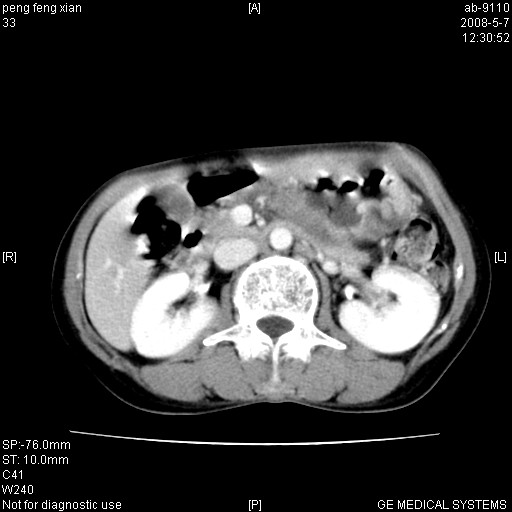

女,56岁。b超左一腹包块,考虑胃肠道肿瘤。

胃壁增厚,左前胸壁局限性隆起,考虑胃癌可能性大,建议做胃镜

典型胃癌胰体尾部受侵。

胃体部胃壁增厚,不均匀性强化,与胰腺分解欠情.

考虑:胃癌,胰腺受侵待除外.

鉴别:胃淋巴瘤(强化不明显)

建议:胃镜检查.